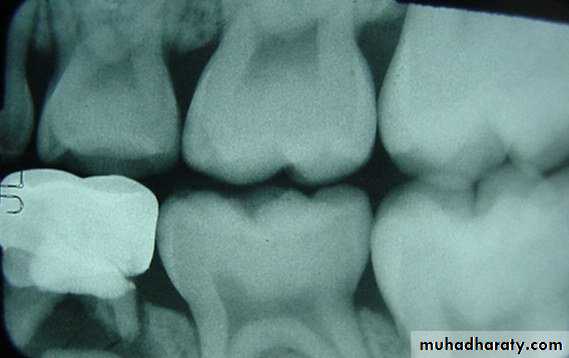

• Radiographic examination.

Class II Amalgam Preps

the contour of the toothClass II Amalgam Preps

• a) gingival floor position• b) box is perpendicular to long axis

• c) rounded angles

• d) Rounded axiopulpal line angle

• e) wide Contact area

• f) No bevel at gingival margins